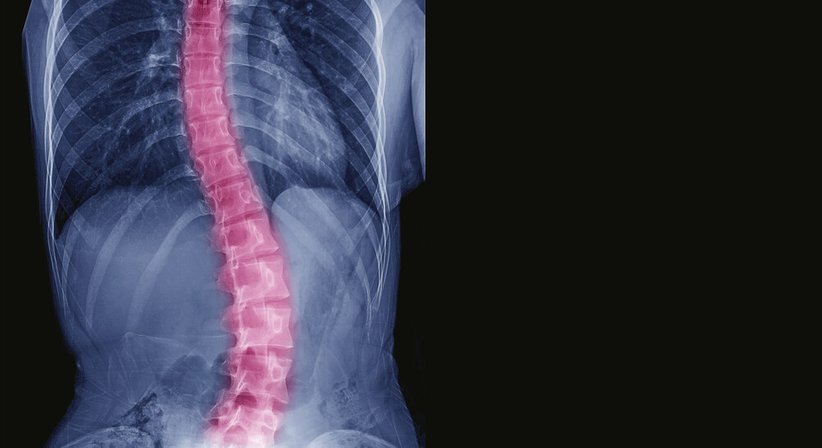

Bei einer Skoliose handelt es sich um eine Seitenabweichung der Wirbelsäule von der Längsachse, meist mit einer Rotation der Wirbelkörper – die Wirbelsäule wächst sozusagen in eine fehlerhafte Verdrehung hinein bzw. verkrümmt sich zur Seite.

Die Therapie beruht auf einer umfassenden Abklärung und exakten Diagnose und wird für jeden Patienten entsprechend der individuellen Umstände und Bedürfnisse individuell erarbeitet.Eine besonders wichtige Rolle für die Behandlungsplanung spielen, neben anderen Faktoren, der Schweregrad der Skoliose (u. a. ermittelt anhand des COBB-Winkels, welcher auf den Röntgenbildern für die Abschnitte der verdrehten Wirbelsäule ausgemessen wird), die Skolioseform, das Krümmungsmuster, das Alter und die körperliche Verfassung.